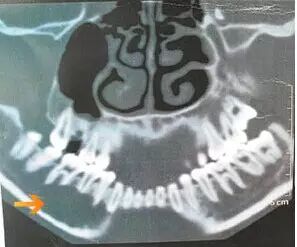

CT 示下颌骨溶骨性破坏,病变累及的牙齿牙根吸收。病变下颌骨骨皮质未见侵蚀。